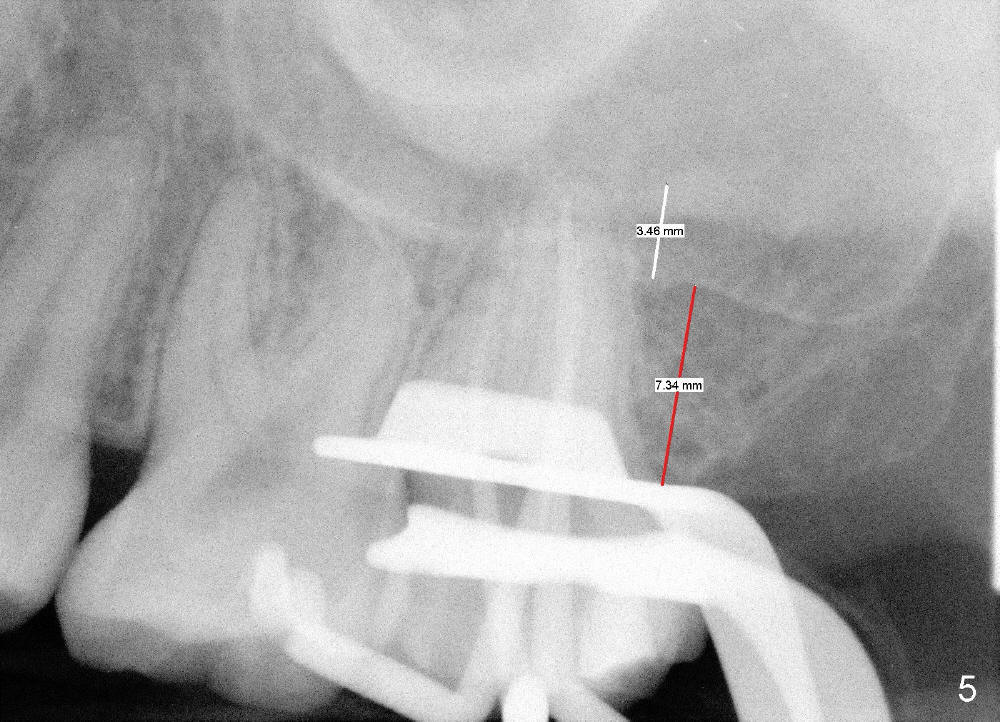

昨天在左上七做根管治疗(图四),二十一岁女孩,嘴巴小,做的很辛苦,术中拍摄根尖片(图五),突然领悟到一个道理。由于上颌窦底板骨皮质明显(图四红箭头),我们认为上颌骨高度仅仅由黑箭头表示。其实一部分根尖深入上颌窦,那里必有骨质,所以上颌骨高度应该由两部分组成(图五:3.46mm

+ 7.54mm),而且最后三个毫米可能对条件不好病例植牙有帮助(例如徐博病例)。